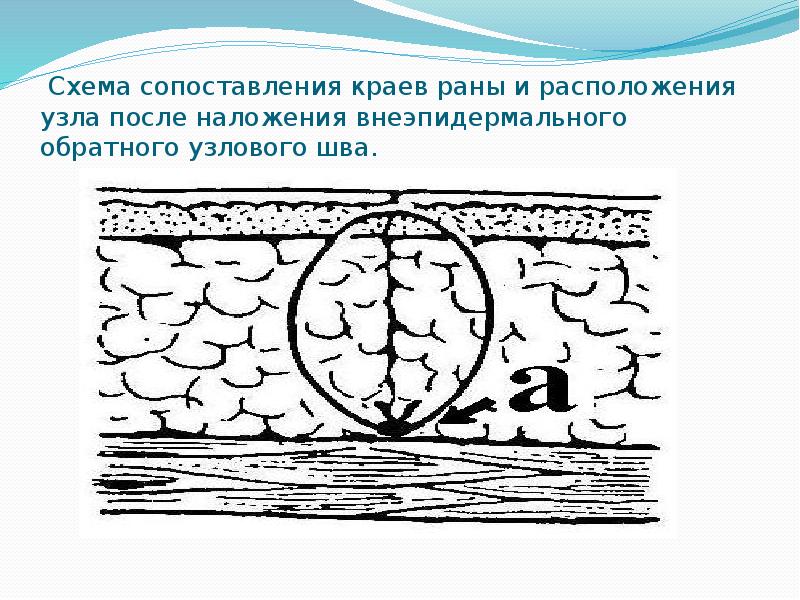

- 57. Схема сопоставления краев раны и расположения узла после наложения внеэпидермального обратного